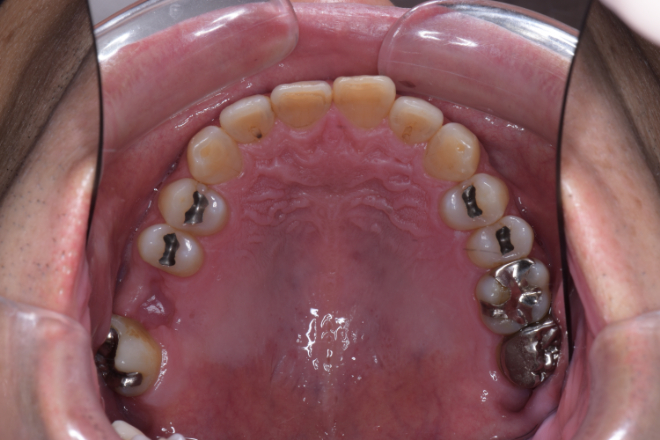

| 備考 | 右上の欠損部へのインプラントを希望で来院されました。 左下のブリッジの下にものが挟まりやすいとのことでブリッジ部分もインプラント埋入を希望されました。口腔内の銀歯も全て綺麗にやりかえたいとのことで、ダイレクトボンディングやセラミックインレーやジルコニアクラウンでやりかえていきました。 右上6番のインプラント埋入時にはソケットリフトで骨造成を行なっています。 見た目だけではなく噛みやすくなりとても満足されています。現在はエアフローのクリーニングやホワイトニングで通院されています。 |